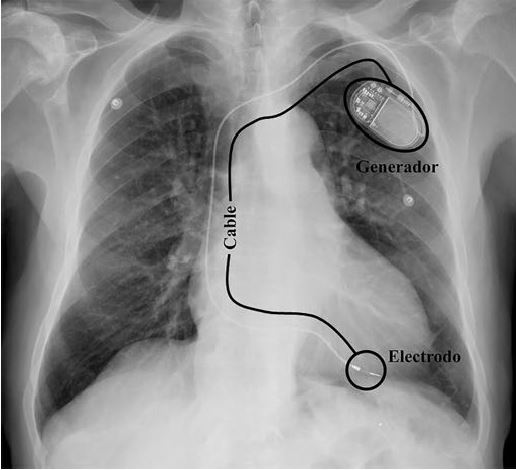

Gran trabajo de los compañeros del Servicio Radiología Arrixaca En la imagen podréis ver cómo son las estructuras y anatomía que debe ver un profesional de la #Radiología para rastrear la vía aérea superior por #Ecografía Los #TSID pueden aprender y realizar este mapeo perfectamente